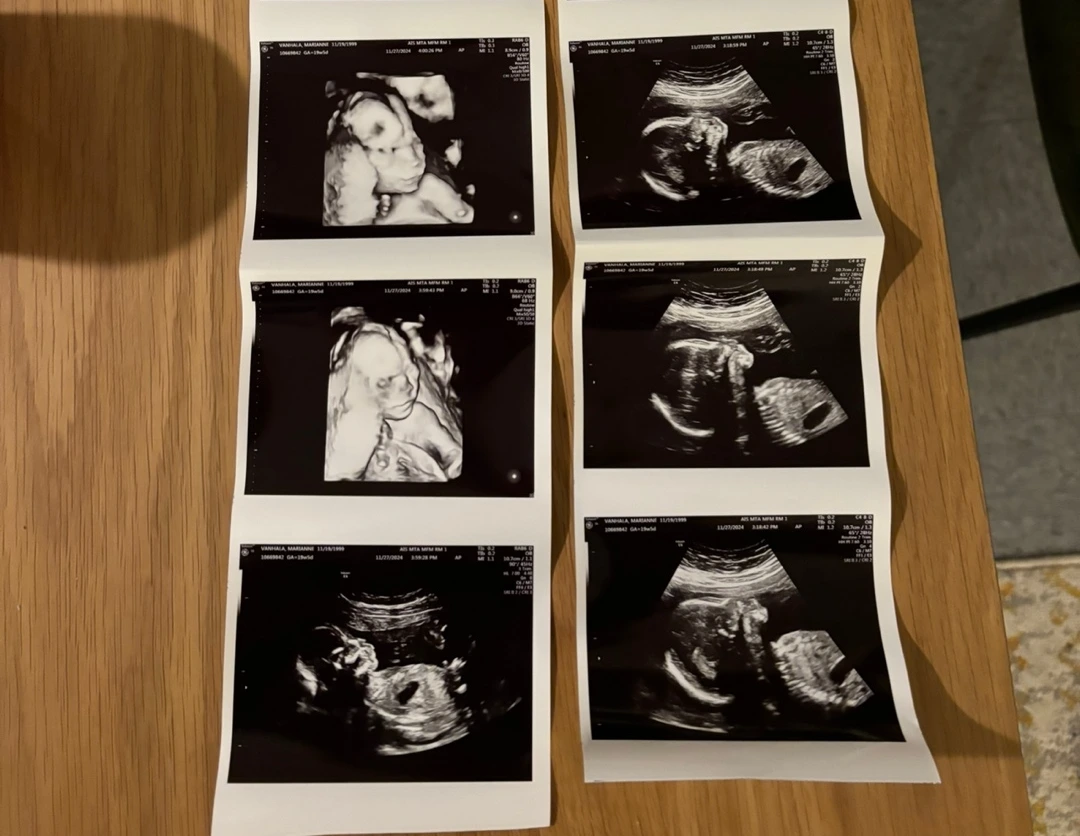

2025년 새해가 밝았다. 2025년 내게 일어나는 가장 큰 변화는 미국 보스턴에서 혼혈아기의 아빠가 된다는 것이다. 한국 나이로 30살이 된다는 사실에 많은 주변 친구들이 부담을 느낀다. 나는 워낙 거대한 "아빠"라는 이름의 깊이에 30살이라는 조그마한 웅덩이는 크게 느껴지지 않는다. 지금까지 삶에서 이런저런 변화들이 일어났지만, 아빠가 된다는 것만큼 내 삶에 큰 영향을 끼치는 것은 없는 것 같다. 아직 아들이 태어나지 않았지만, 태동을 느끼기 시작하고 이름을 정하고 나니 아빠가 된다는 것이 정말로 실감이 난다. 이름도 정했다. 새해도 되었고, 아이는 곧 태어난다. 이런 감정을 바탕으로 무엇이 달라지고 있는지, 앞으로는 어떻게 살고 싶은지 한번 공유해보고자 한다.

KakaoTalk_Photo_2024-11-30-14-09-35.jpeg